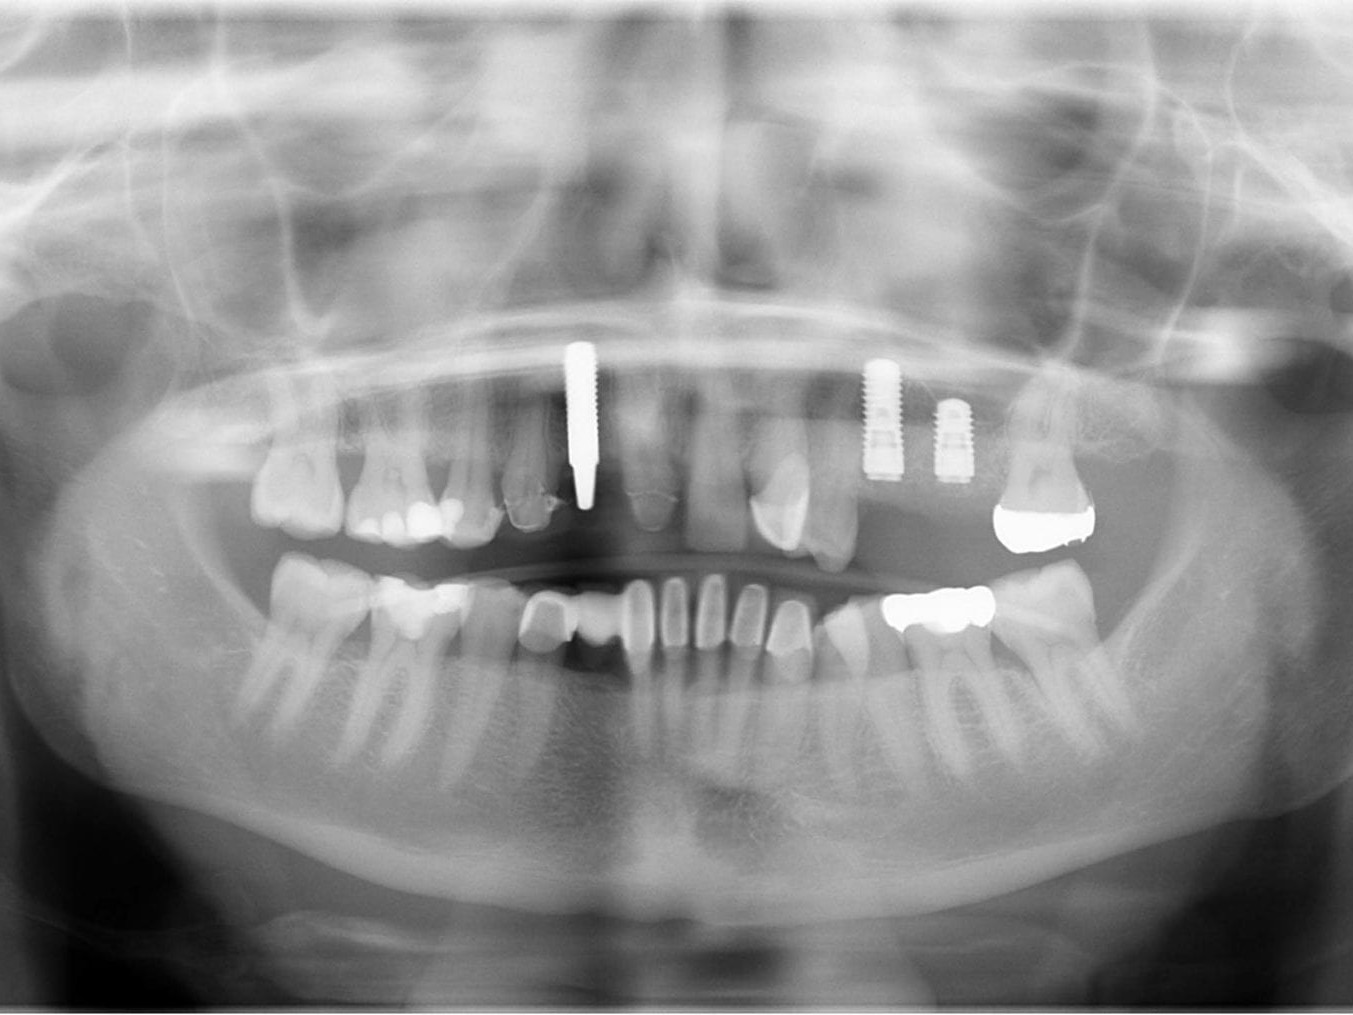

Abb 1 Präoperatives Orthopantomogramm

Abb. 1: Präoperatives Orthopantomogramm

Abb 21 Postoperatives Orthopantomogramm

Abb. 21: Postoperatives Orthopantomogramm